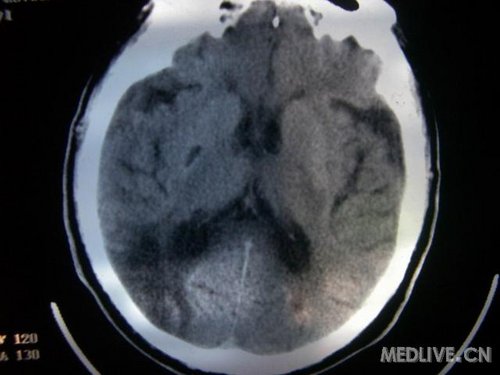

病人男性 73岁 市民 以“幻听、幻视两天,言语含糊、精神错乱一天”入院。

两天前无诱因出现幻听、幻视,描素眼前有彩色的圆圈,听见有人说话(但说什么不详),一天前出现胡言乱语,言语含糊,精神错乱,问话不答,行走略有不稳,来我院就诊,门诊头CT检查:(下面有片)入院后查体不合作,表情淡漠,问话不答,大致检查了一下,颅神经未见明显异常,颈软,右手活动似忽略差。其他检查不配合。脑电图:广泛轻-中度异常。

既往史:半年前曾患“右侧脑梗塞”但无明显后遗症,生活能自理,无高血压、糖尿病、心脏病史。

先传半年前的片子:

此次入院时的片子: